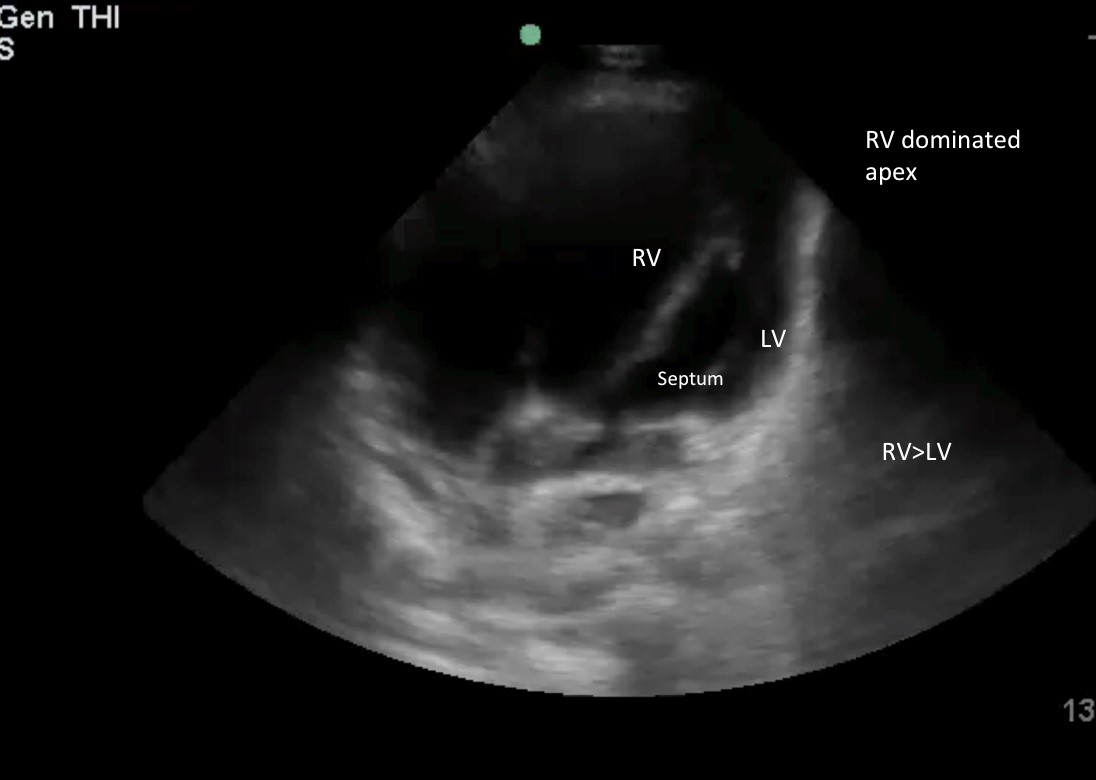

画像4: RVサイズ > LVサイズの⅔ 頂点がRVに支配されている